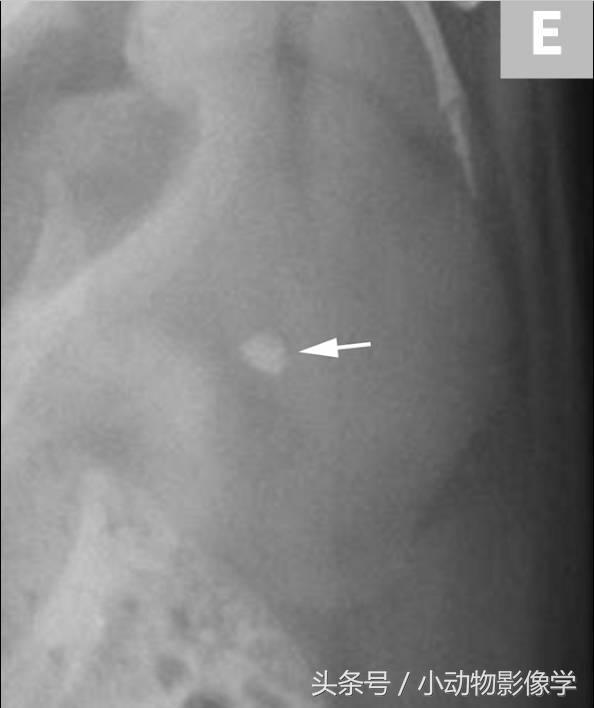

图3E、这是另一只狗左肾X光片的特写,肾盂区域内有小型肾结石(箭头)。

图3F、图3E中左肾的超声图像。与图3B和3D相比,由于该犬的结石(箭头)体积较小,所以远端声影伪像很小(三角箭头)。